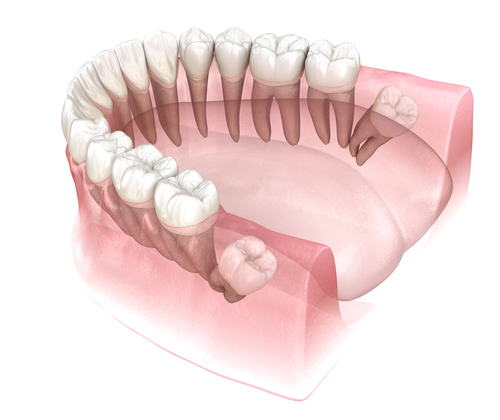

사랑니는 입안 가장 뒤쪽에서

올라오는 치아이기 때문에,

다른 치아와 달리 방향과 공간의

영향을 크게 받습니다.

턱뼈의 공간이 넉넉하지 않은 경우에는

제자리로 올라오지 못하고 옆으로

눕거나 뒤쪽을 향해 자리

잡기도 해요.

또 하나는 사랑니가 옆 치아를 향해

누워 있는 경우로,

이 방향은 시간이 지날수록 옆

치아를 밀어내려는 힘이

커질 수 있어 전체적인 치아 흐름에

부담이 생길 수 있습니다.